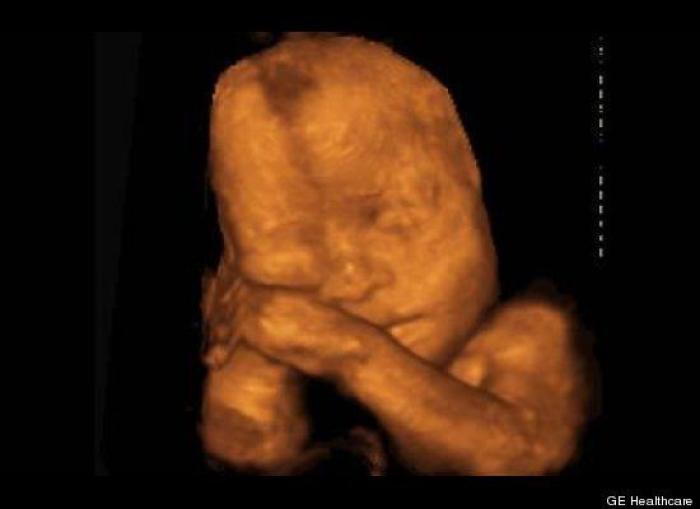

En esta galería puedes ver en fotos como es el desarrollo de un feto de semana en semana:

Desarrollo del feto, en fotos